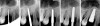

Figure 10 shows a missing maxillary left first bicuspid tooth. An envelope incision with full flap reflection was used to reveal division A ridge width.6 OD burs were then used to create an implant osteotomy (Figure 11). As per protocol, appropriate osteotomy diameter was created with the successive use of OD burs followed by the application of a bone grafting putty (NovaBone®, NovaBone Products, LLC, novabone.com) via the crestal osteotomy. The bone putty was introduced to the site (Figure 12), and OD burs were used to propel the graft apically beneath the sinus membrane (Figure 13). Implant placement was performed and the flaps were sutured closed with 3.0 PTFE sutures (Figure 14). The additional bone graft at the apical portion of the implant site after implant placement was demonstrated through a series of intraoperative x-rays (Figure 15).

Fig 15. A series of intraoperative x-rays demonstrating sequential use of OD burs along with graft and implant placement. Note graft confinement at the apex of the implant indicating intact Schneiderian membrane.

Figure 15